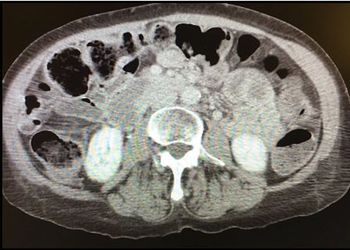

A 35 y/o woman presents with 3 wks lower abdominal pain that's worse with movement. Review exam, labs, CT scan. Your diagnosis?